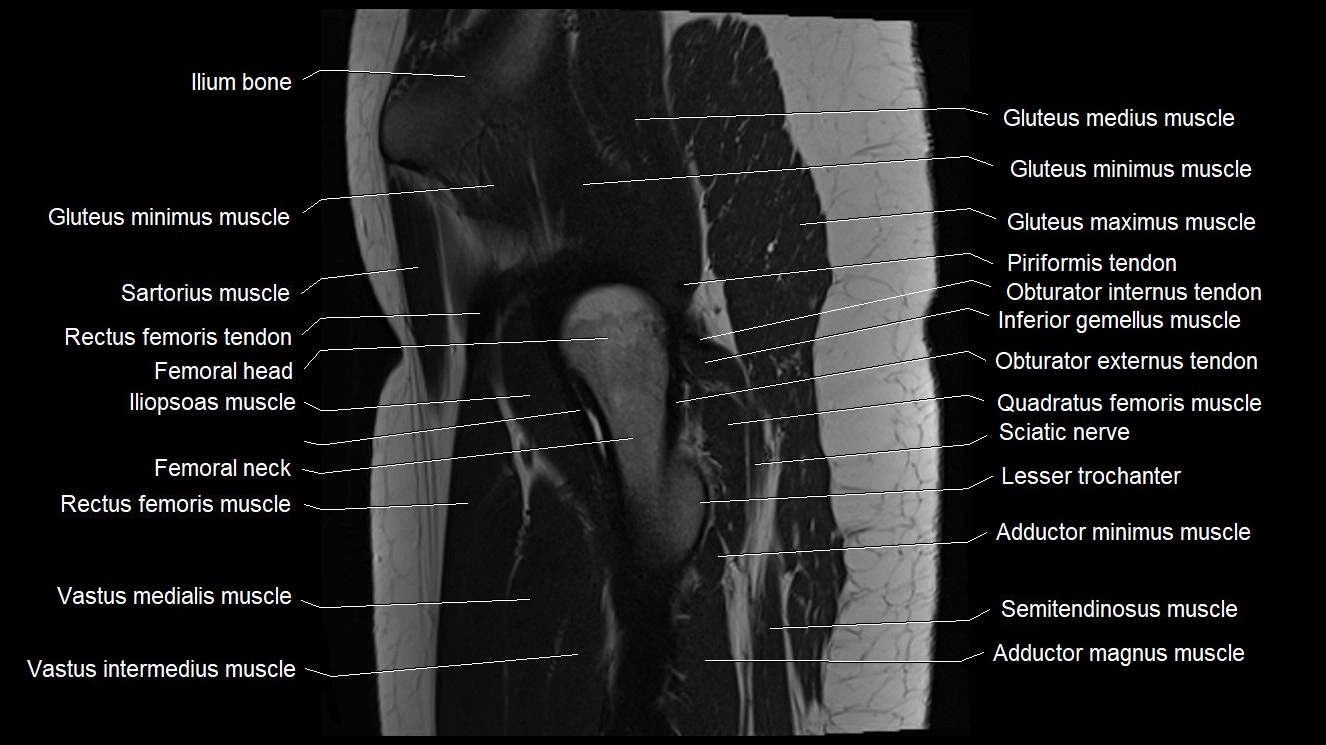

- Gluteus maximus muscle

- Gluteus medius muscle

- Gluteus minimus muscle

- Gluteus minimus tendon

- Greater trochanter

- Head of femur

- Iliopsoas muscle

- Iliopsoas tendon

- Iliotibial tract

- Inferior gemellus muscle

- Lesser trochanter

- Neck of femur

- Quadratus femoris muscle

- Rectus femoris muscle

- Rectus femoris tendon (Proximal tendon of rectus femoris)

- Sartorius muscle

- Vastus intermedius muscle

- Vastus medialis muscle